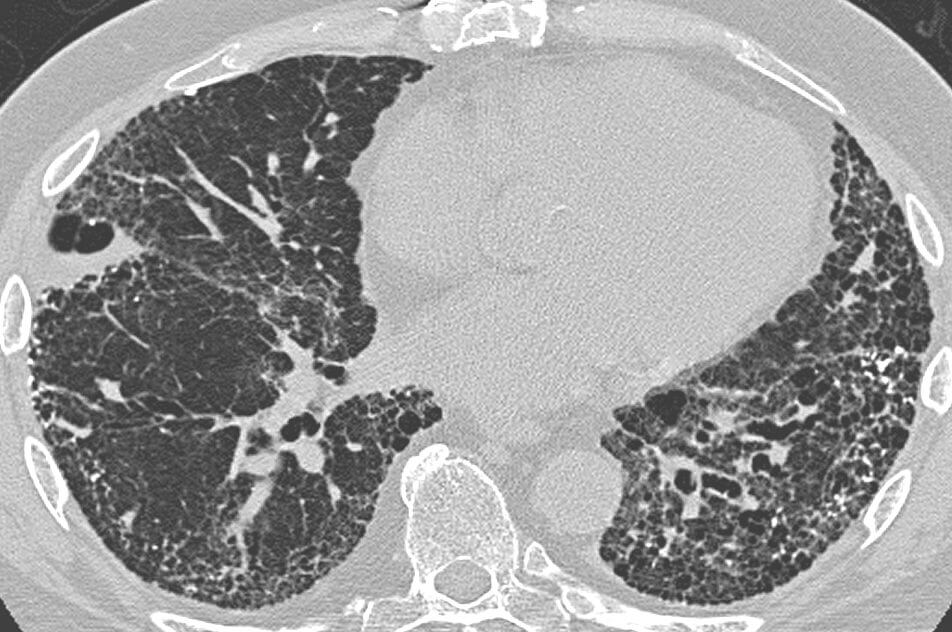

Figure 1: Honeycomb Lungs

CT scan in a patient with usual interstitial pneumonia, showing interstitial thickening, architectural distortion, honeycombing and bronchiectasis.